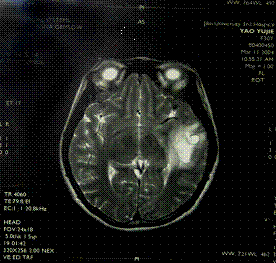

腦梗塞器質性精神障礙是一組由腦部疾病或軀體疾病導致的精神障礙。由腦部疾病導致的精神障礙,包括腦變性疾病、腦血管病、顱內感染、腦外傷、腦瘤等所致精神障礙。軀體疾病導致的精神障礙只是原發軀體疾病症狀的組成部分,也可與感染、中毒性精神障礙統稱為症狀性精神障礙。一般常見類型有:

2、多發腦梗塞性精神障礙。由於腦動脈硬化影響大腦血液供應,特別是反覆發作的腦血管意外所致的痴呆綜合徵。腦外部動脈(頸動脈或錐基底動脈)硬化斑的微栓子或缺血引起大腦白質中心散在性多數小梗塞灶所致,因而稱為多發梗塞性痴呆。本病多在中老年起病,據上海的資料,約占住院的精神病人的1%左右,男性略多於女性。病程多呈階梯式發展,常可伴有局限性神經系統體徵。